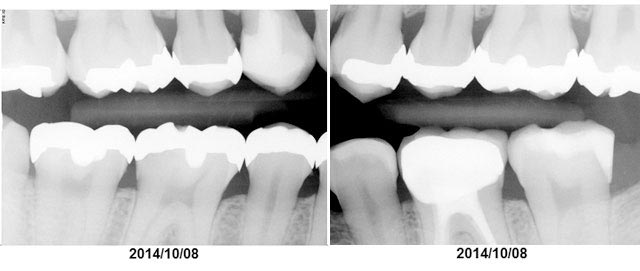

2.レントゲン

英語ではX-rayと呼ぶ方が一般的です。左右1枚ずつのレントゲンを撮ります。歯と歯の間に虫歯や歯石が無いか、歯を支えている骨が痩せていないか、詰め物や銀歯の状態は大丈夫か、などを知ることができます。